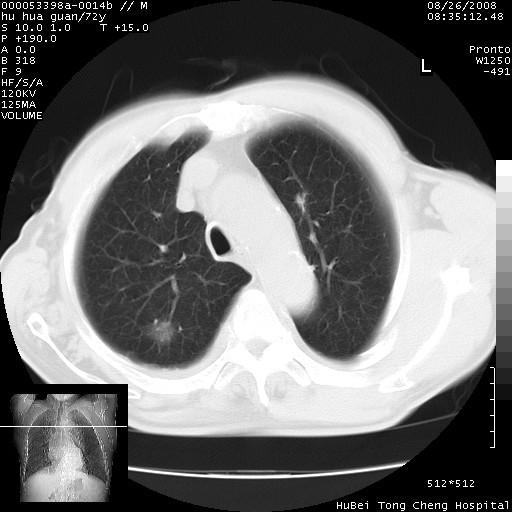

可以明确的说。肯定不是主动脉夹层破裂出血!考虑为淋巴瘤或间叶组织来源的恶性肿瘤可能性大。右肺小结节建议薄层观察,如能发现恶性征象,那椎前改变就考虑为转移所致。至于双侧少量胸水乃静脉血回流受阻所致。

1、右肺周围性肺癌、胸腔积液(双)

1、右上肺结节病变,肺泡癌不除外,请随诊;左下肺近后纵隔病变,考虑纵隔型肺癌侵犯大血管可能;

2、右下肺背段少许炎症,双侧胸腔积液,右下肺纤维索条。

建议排除结核引起的冷脓肿。